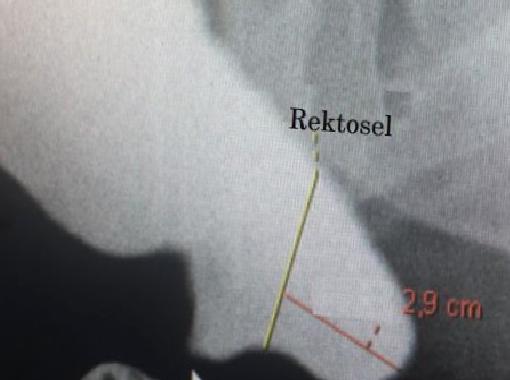

REKTOSEL Şekilde daire içerisinde gösterilmiş barsağın son kısmında dışkılama, ıkınma sırasında balonlama meydana gelmekte, dışkı, normal yolunun dışına kaçmaktadır.

REKTOSEL Şekilde balonlamış barsak görülmektedir. Bu hastalar, dışkılama sırasında tam boşalamamakta, uzun süre ıkındıktan sonra yorulmaktadırlar. Yetersiz, eksik boşalma hissi ile tuvaletten çıkmakta, bir süre yürüdükten, bekledikten sonra yeniden dışkılama isteği ile tuvalete girmektedirler.